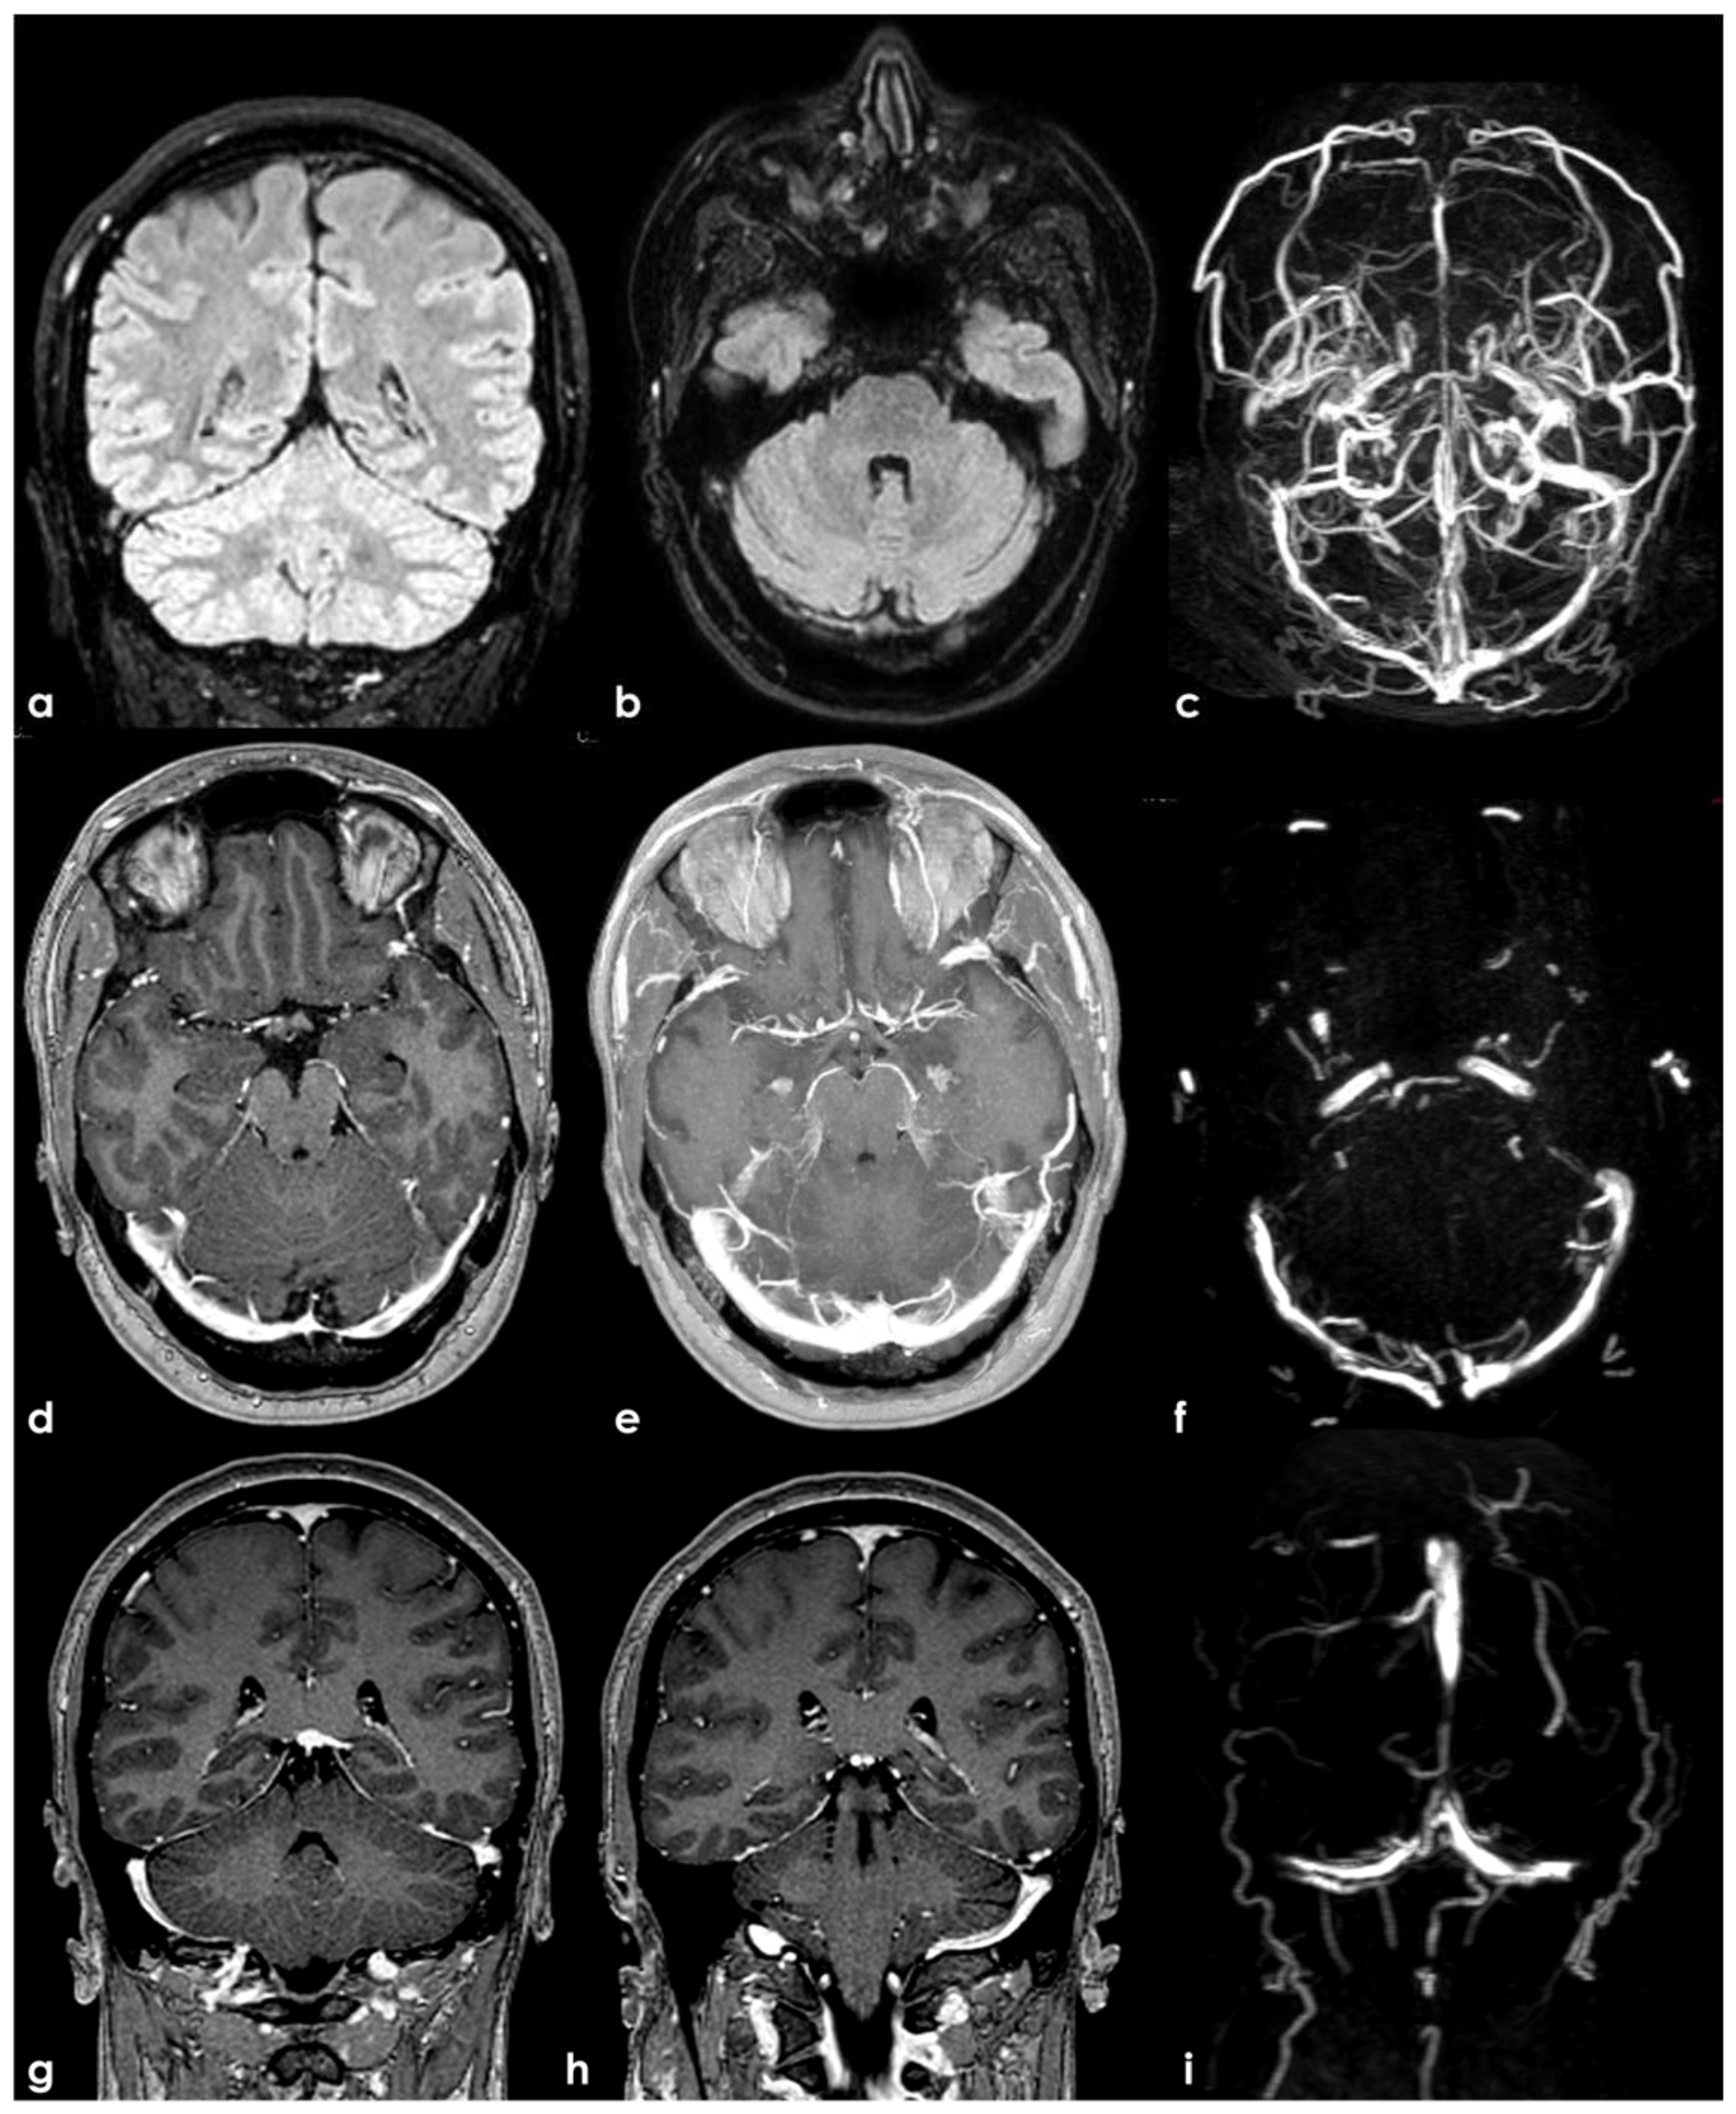

4.1.2. Arachnoid Granulations

- Leach, J.L.; Jones, B.V.; Tomsick, T.A.; Stewart, C.A.; Balko, M.G. Normal appearance of arachnoid granulations on contrast-enhanced CT and MR of the brain: Differentiation from dural sinus disease. AJNR Am. J. Neuroradiol. 1996, 17, 1523–1532. [Google Scholar]

- Roche, J.; Warner, D. Arachnoid granulations in the transverse and sigmoid sinuses: CT, MR, and MR angiographic appearance of a normal anatomic variation. AJNR Am. J. Neuroradiol. 1996, 17, 677–683. [Google Scholar]

- Leach, J.; Meyer, K.; Jones, B.; Tomsick, T. Large arachnoid granulations involving the dorsal superior sagittal sinus: Findings on MR imaging and MR venography. Am. J. Neuroradiol. 2008, 29, 1335–1339. [Google Scholar] [CrossRef]

- Haroun, A.; Mahafza, W.; Al Najar, M. Arachnoid granulations in the cerebral dural sinuses as demonstrated by con-trast-enhanced 3D magnetic resonance venography. Surg. Radiol. Anat. 2007, 29, 323–328. [Google Scholar] [CrossRef]